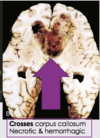

- Glioblastoma **

- Grade II/IV: Diffuse astrocytoma

- Grade III/IV: Anaplastic astrocytoma

- Grade IV/IV: Glioblastoma (this is malignant)